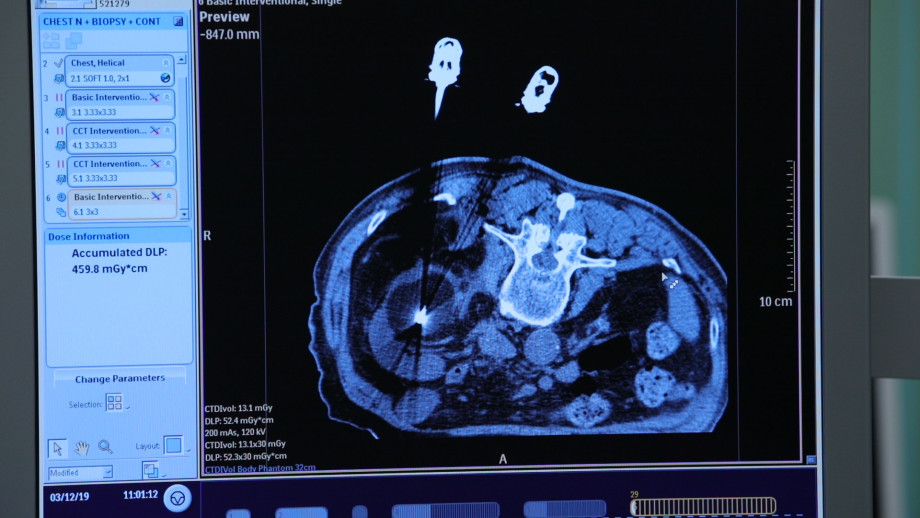

На западе инженеры сумели изготовить специальные иглы, их называют зондами. Это своего рода проводник, который доставляет холод к новообразованию. Но диаметр такой иголки был большим – почти 4 миллиметра.

Нужен был миниатюрный инструмент, который помог бы заморозить опухоль и при этом не повредил бы здоровые ткани. Прохоров приступил к разработке зонда в одиночку – тогда ученого никто не поддержал. Мало кто верил в его успех – и теоретики, и практики говорили, что это невозможно. Казалось, все было против профессора. Когда проект был готов, во всей стране не нашлось мастера, который сумел бы по чертежам изготовить криозонд, слишком «тонкой» была работа. «Левшу» ученый отыскал в Петербурге совершенно случайно. Только два человека попытались соединить металлические капилляры герметичной сваркой, и только у чудо-мастера инженера Гурина Александра Владимировича получилось.